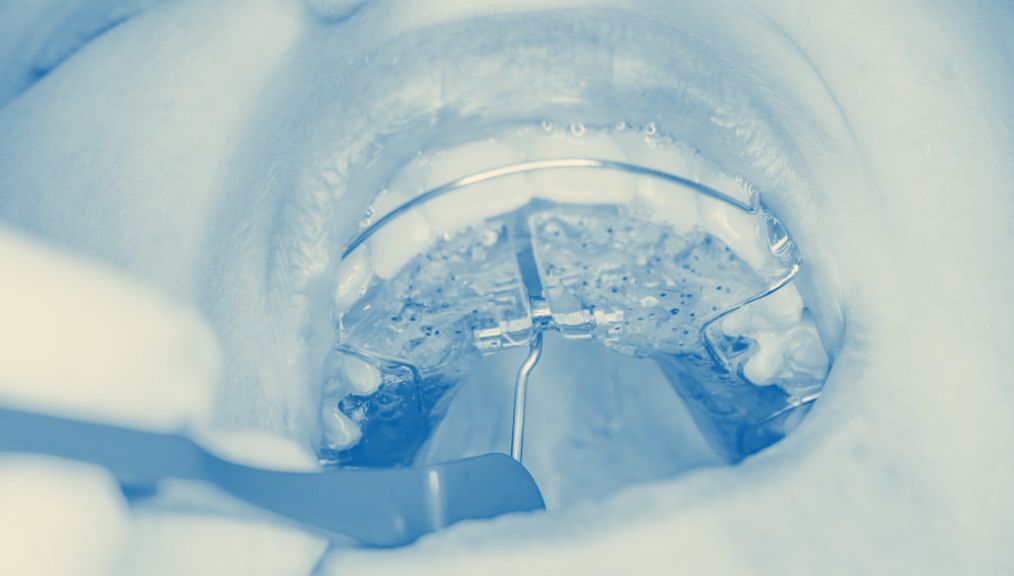

• Palatal expanders or other devices: In some cases, gentle orthodontic appliances can help widen the palate, creating space for teeth and improving airway function.

palatal-expansion-children-dentist-central-ab

palatal-expander-kids-dentist-central-ab